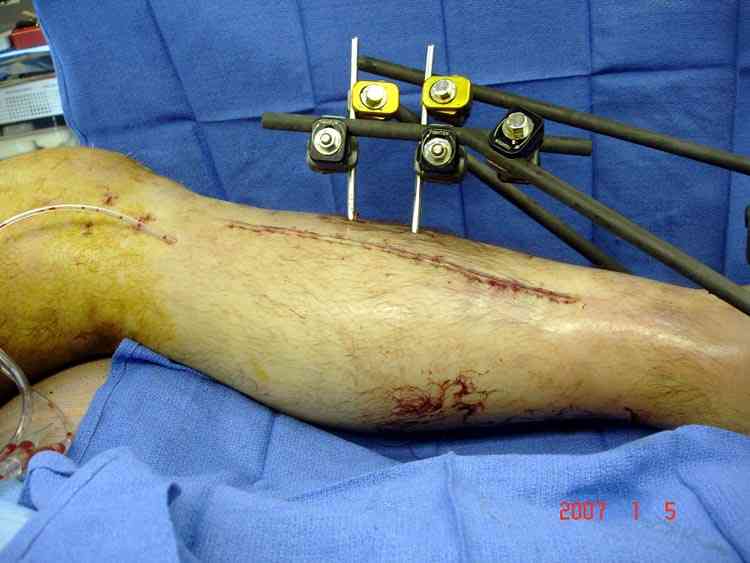

Отечность в зоне фиксации является противопоказанием к открытому методу. Для профилактики осложнений с фиксацией можно повременить применением стабилизирующего наружного фиксатора. Фиксатор восстанавливает длину конечности, облегчает в будущем репозицию и создает благоприятные условии для спадения отека. Также позволяет экономить средства, вместо дорогого стационара больной может находится на амбулаторном наблюдении. Появление симптома "skin wrinkle test" (морщинки) подскажет о готовности кожного покрова для окончательной операции на костях.

На фото результат от Derma Closure, аппарата, предназначенного для трудно закрываемых дефектов кожных покровов.

Множественная огнестрельная травма конечностей, перелом костей предплечья, фиксация в первые часы и дефект мягких тканей, мероприятия по закрытию...